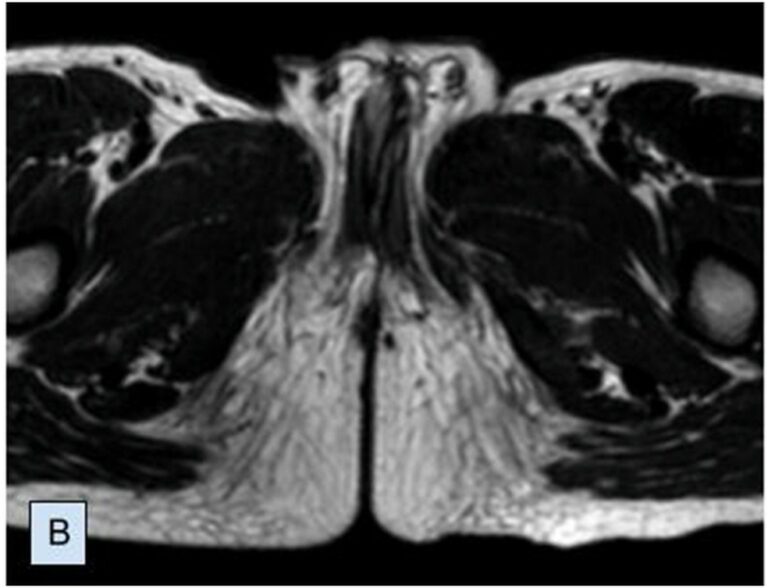

“A princípio, não há uma necessidade de esperar muito tempo para corrigir – se tiver todo o diagnóstico, porque, para você saber quantos corpos cavernosos [existem], precisa ter uma ressonância magnética para avaliar”, pondera.